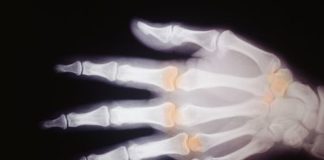

Tag: artrite reumatoide

Tofacitinib citrato per l’artrite reumatoide attiva da moderata a grave

Certolizumab pegol per l’artrite reumatoide

Studio di fase III

Sarilumab vs adalimumab per l’artrite reumatoide

Sarilumab vs adalimumab per l'artrite reumatoide dimostra superiorità nel migliorare segni e sintomi alla settimana 24 di trattamento